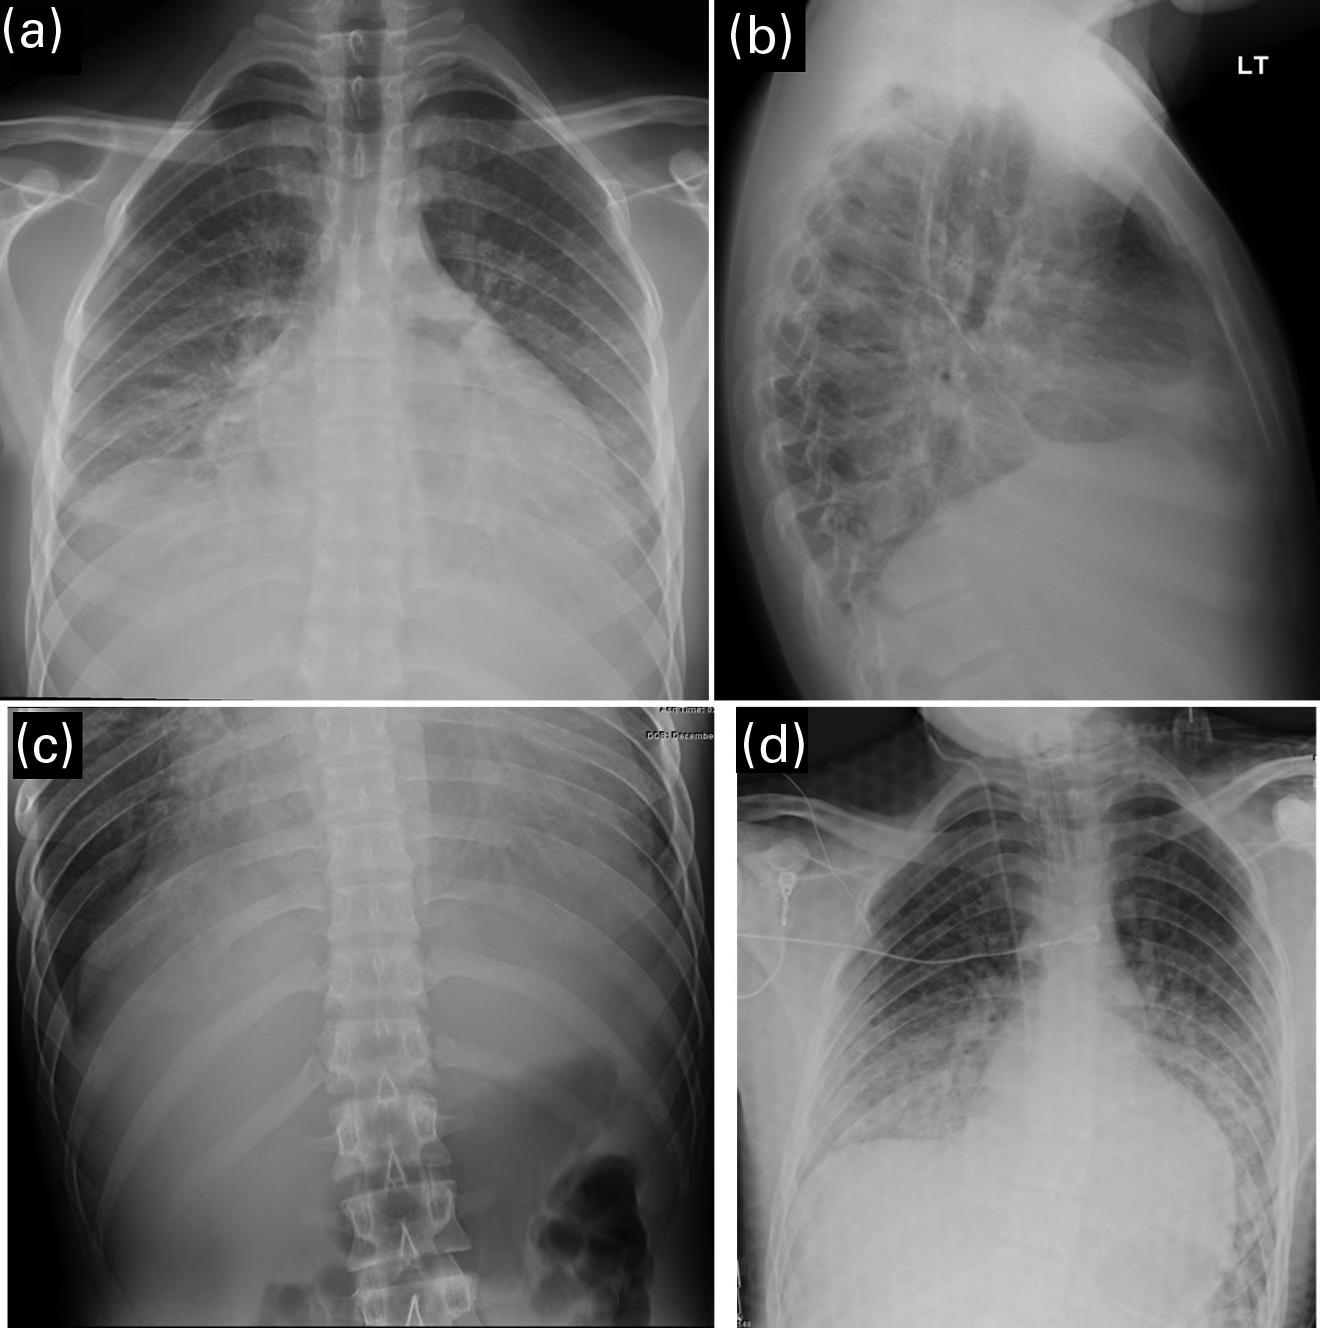

The clinicians for this patient started with a chest radiograph. The initial chest radiographic identified small pleural effusions and interlobular septal thickening, which were suggestive of interstitial pulmonary edema (see Figures 1.1a and 1.1b). Findings become more apparent when compared with a normal 16-year-old’s chest radiographs (Figures 1.2a and 1.2b). Because of the patient’s vomiting, an abdominal film was also obtained, which demonstrated significant cardiomegaly (see Figure 1.1c), thus leading to the diagnosis of dilated cardiomyopathy and/or pericardial effusion. On the chest radiograph, the reduced lung volumes and elevated hemidiaphragms masked the cardiomegaly, which was more apparent on the better penetrated abdominal radiograph.

Careful attention to the heart, mediastinum, airway, lungs, pleura, bones, and soft tissues is essential to accurately diagnose the cause of chest pain. A screening chest film for patients with chest pain has low sensitivity for structural cardiovascular lesions, such as myocarditis, dissection, or pulmonary infarction, but is helpful in the acute setting to diagnose complications of underlying cardiovascular conditions, such as HF, mediastinal hematoma, or pulmonary infarction. It is also helpful to exclude noncardiac causes of chest pain, including pneumonia, pneumothorax, rib fracture, or an aspirated foreign body (see normal chest radiograph, Figures 1.2a and 1.2b).

FIGURES 1.1 a, 1.1b, 1.1c, AND 1.1d . (a, b) PA and lateral views of the chest demonstrating low lung volumes, pulmonary vascular congestion, interstitial opacities in the lung bases, and bilateral trace pleural fluid; (c) the abdominal radiograph is better penetrated than the chest radiograph, and shows an enlarged cardiac silhouette; and (d) post-procedure chest radiograph showing decreased size of the cardiac silhouette after drainage of the pericardial effusion.

FIGURES 1.2 a AND 1.2 b PA and lateral views of the chest in a normal 16-year-old for comparison (different patient). Note the normal appearance of structures. Contour of descending aorta (white arrowheads), superior mediastinal width between superior vena cava on the right and aortic arch on the left (white thick arrows on right and left side), tracheal air column (black arrow), carina (black arrowhead), and the orientation of the clavicles (thin white arrows). In a properly positioned patient the spinous processes lie midway between the medial ends of the clavicles. The cardiothoracic ratio is measured as the ratio of the cardiac transverse diameter (black thin line) divided by the maximum chest transverse diameter (thick black line). The first and second ribs on the left side are numbered (1, 2).